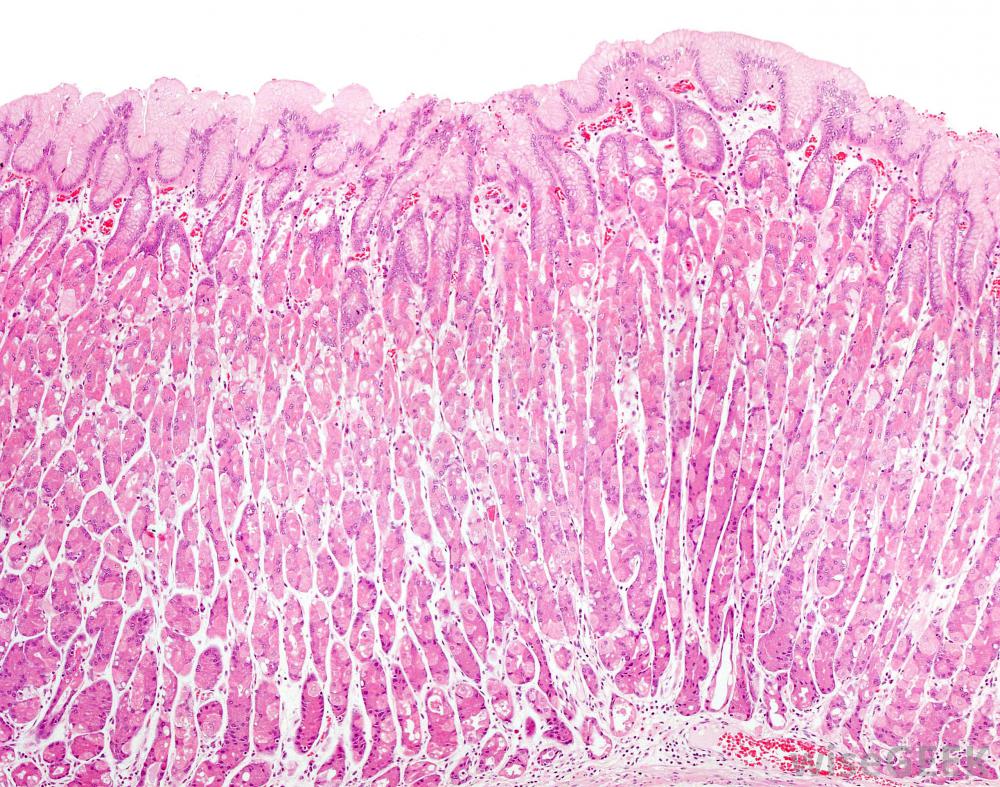

肠溃疡是肠壁上一种疼痛的开放性伤口。肠溃疡的症状可能不同但最常见的症状是胸骨下腹部的剧烈灼痛。这种灼痛时而来,但在两餐之间和清晨很普遍。疼痛的持续时间从几分钟到几小时不等

小肠会形成溃疡,引起恶心和呕吐。